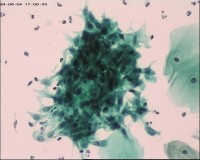

性别

女

年龄

50岁

一般病史

宫颈肥大

标本类型

TCT

制片方法

液基细胞

染色方法

巴氏染色

图1

图2

图3

NILM